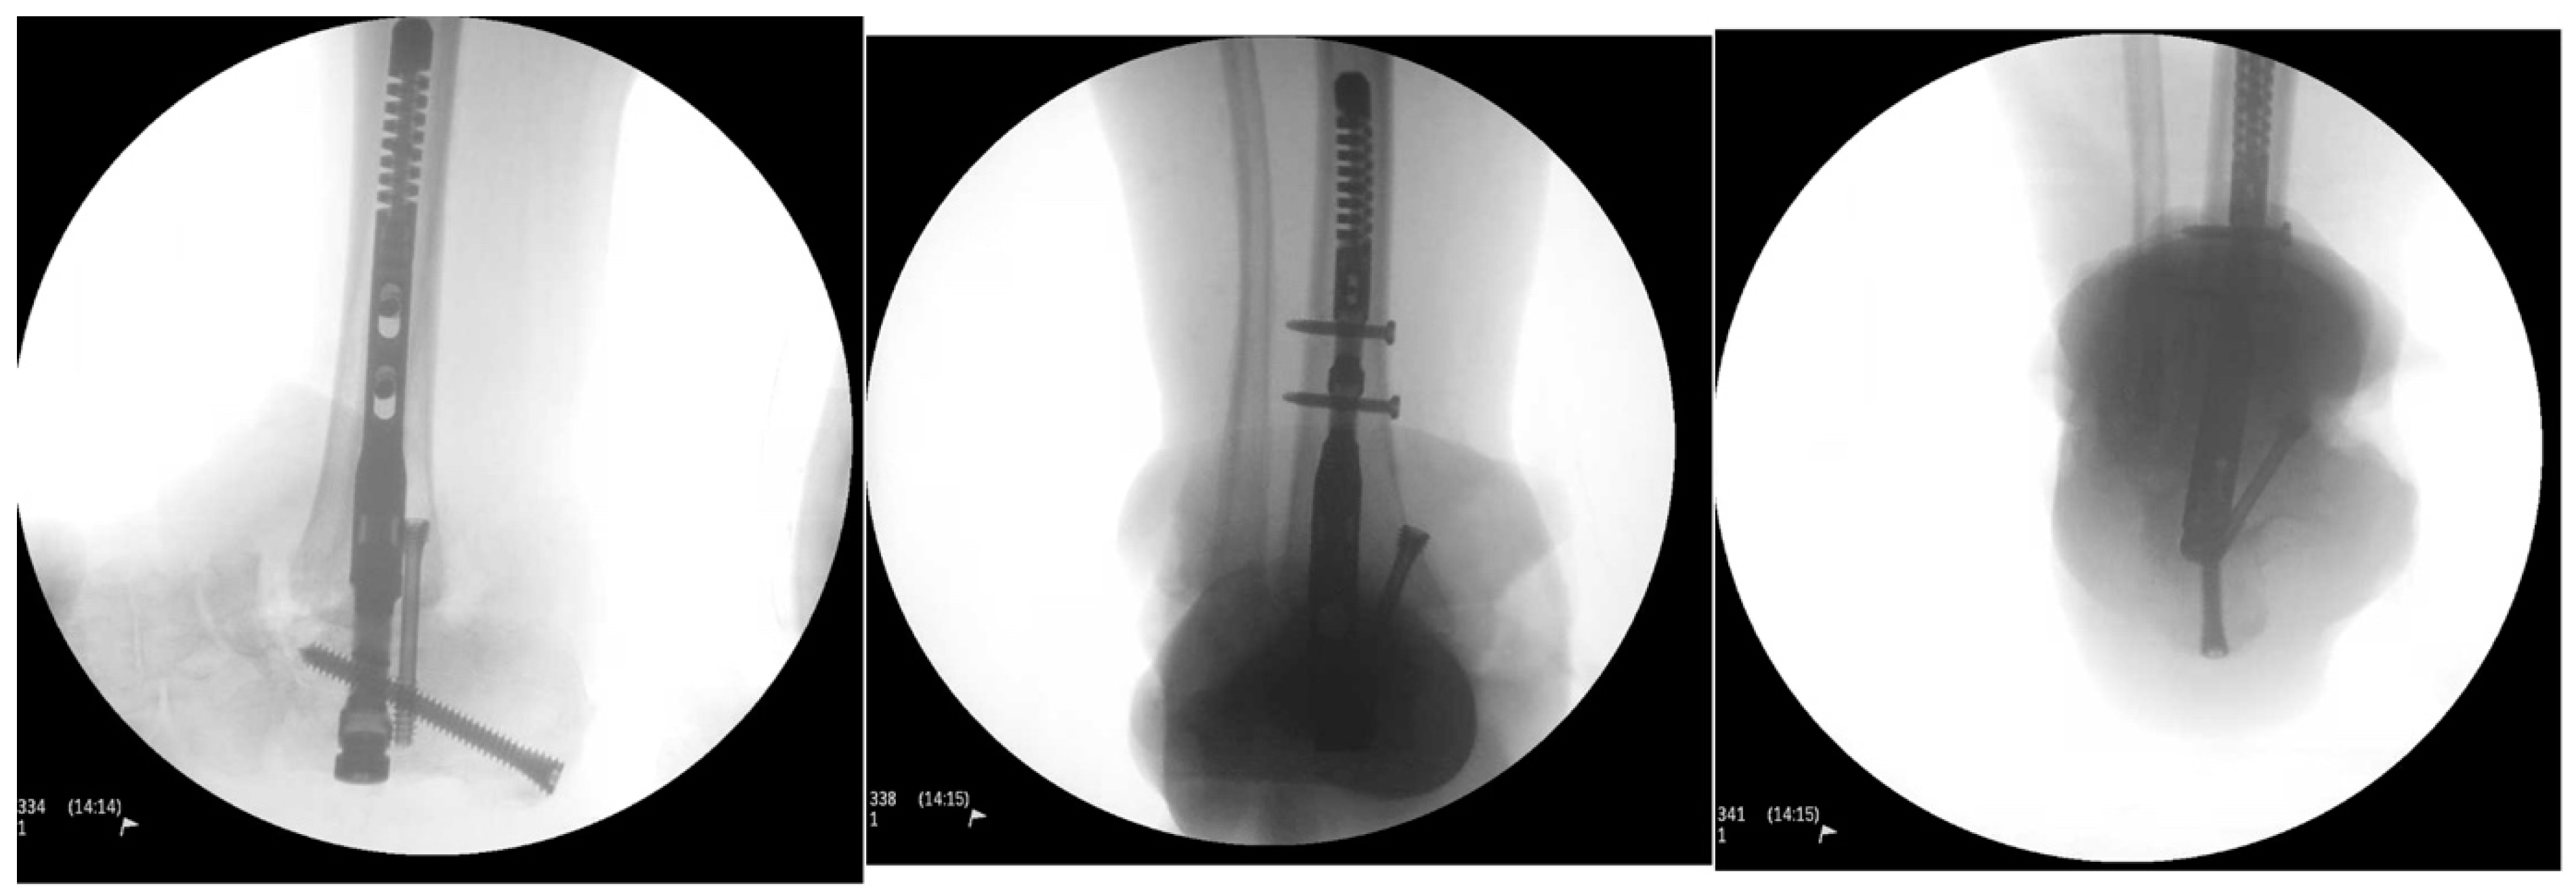

Intraoperative fluoroscopic images confirmed a complete talectomy (Figure 4). This was followed by extensive soft tissue debridement, and a thorough wound lavage. Bone and soft tissue specimens were collected for cultures. The resultant cavity was packed with antibiotic-impregnated cement beads composed of Tobramycin molded on a polydioxanone (PDS) suture. The wound was closed using a nonabsorbable monofilament suture (Figure 5). Sterile dressings were placed, followed by application of a well-padded short-leg posterior plaster splint, which was changed to a cast later (Figure 6).

Figure 4. Intraoperative radiograph.